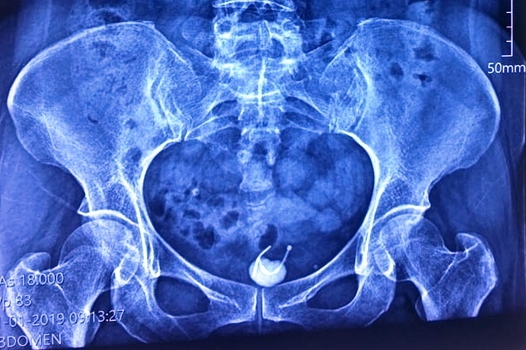

Bệnh nhân nữ đau bụng ở hạn vị kèm theo tiểu khó, qua thăm khám chụp X-quang bác sĩ phát hiện thủ phạm là chiếc vòng tránh thai cũ xuyên qua bàng quang.